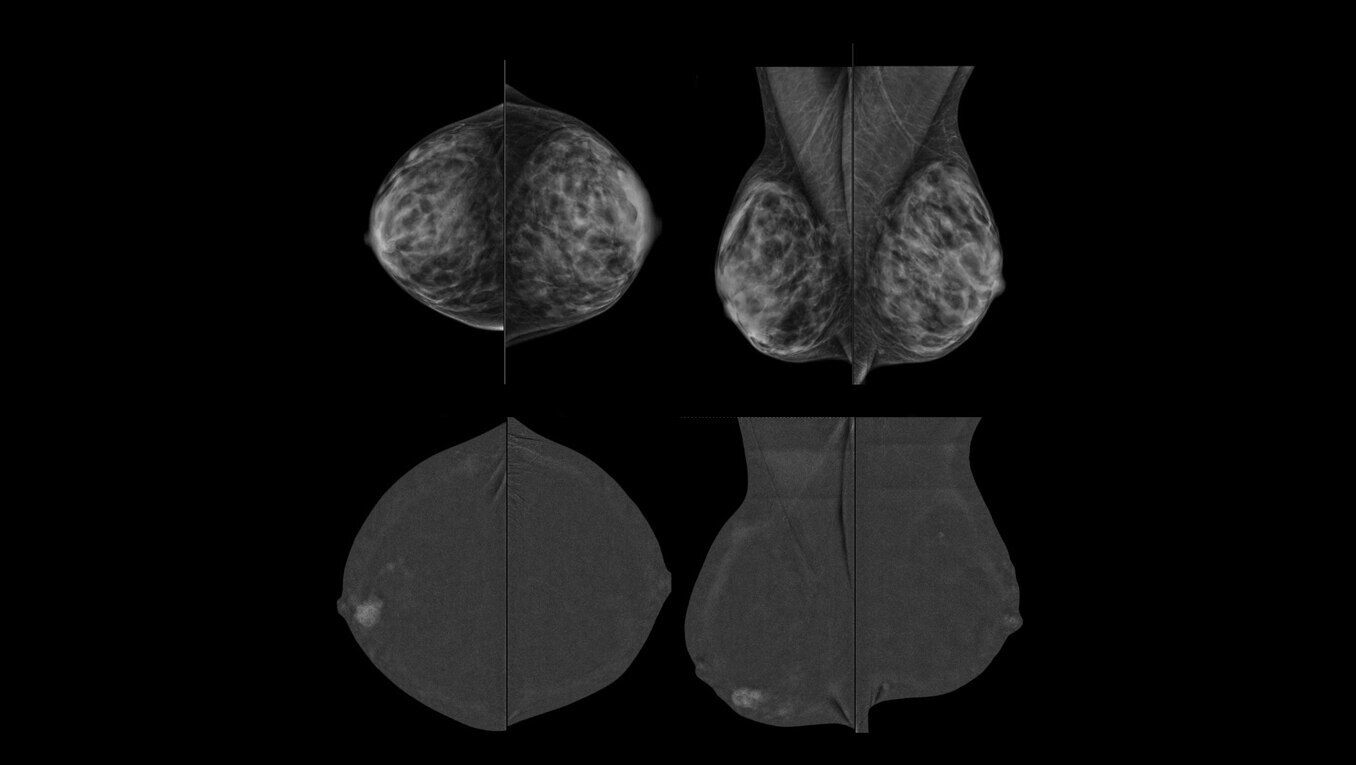

Serena Bright™

Contrast-guided biopsy solution

Utilizes contrast-spectral mammography to clearly target and biopsy lesions without leaving the mammography suite.